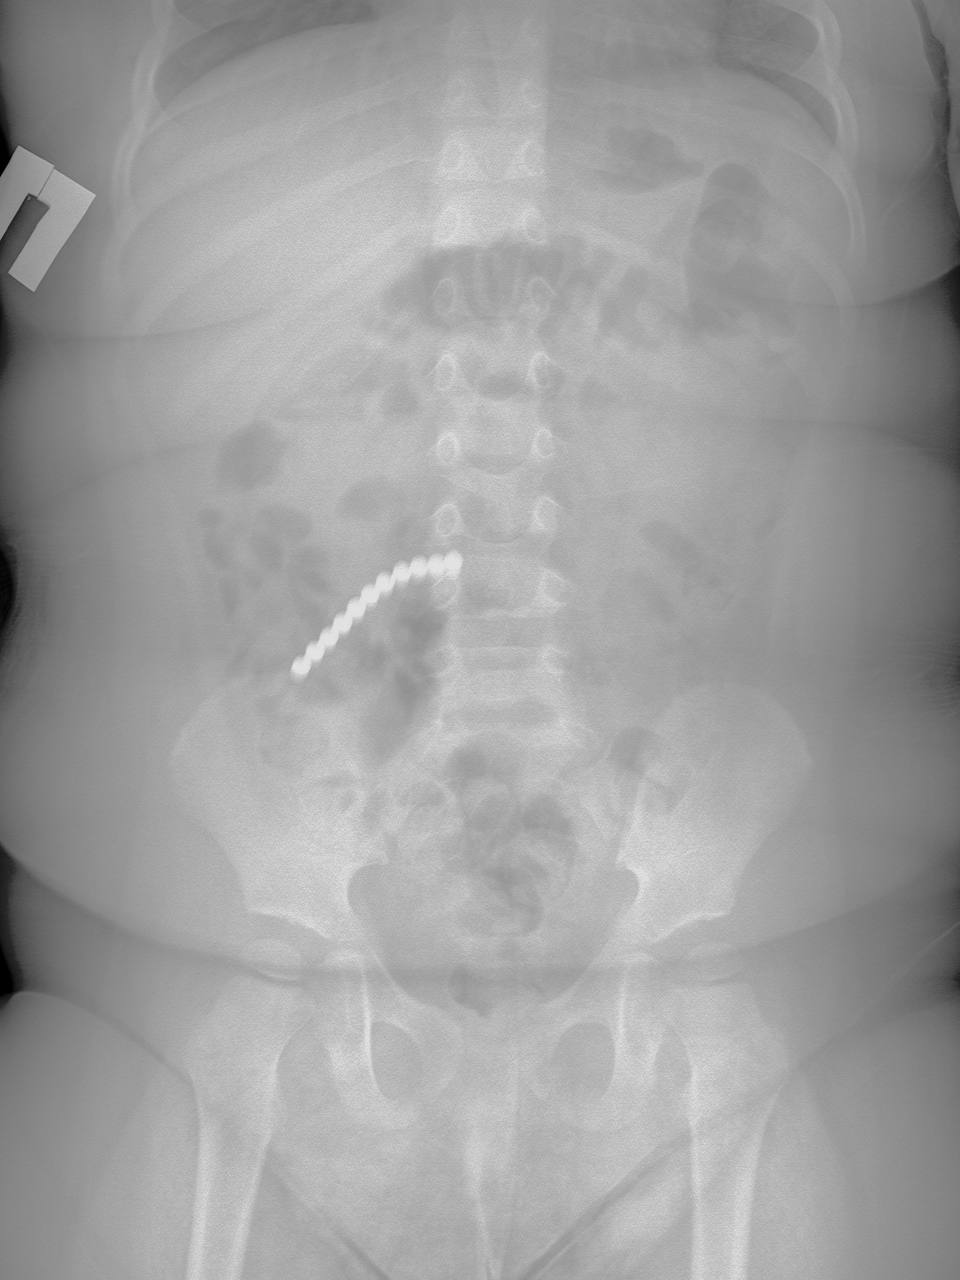

Двухлетний ребёнок из Бурятии проглотил 20 магнитов

В его желудке оказались магнитные шарики от конструктора, которые привели к перфорации кишечника. Это потребовало экстренной операции с удалением части тонкой кишки и аппендикса. К счастью, врачам удалось спасти малыша. Над его лечением работала команда из шести специалистов, включающая хирургов и медицинских сестёр. Сейчас ребёнок переведен в отделение для дальнейшего восстановления, сообщили в ДРКБ.